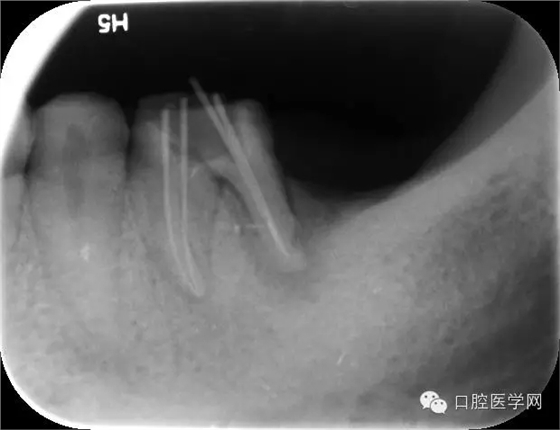

開髓引流,擴(kuò)洗根管,測長;

Protaper擴(kuò)根,試尖,封藥;

根充,拍片。